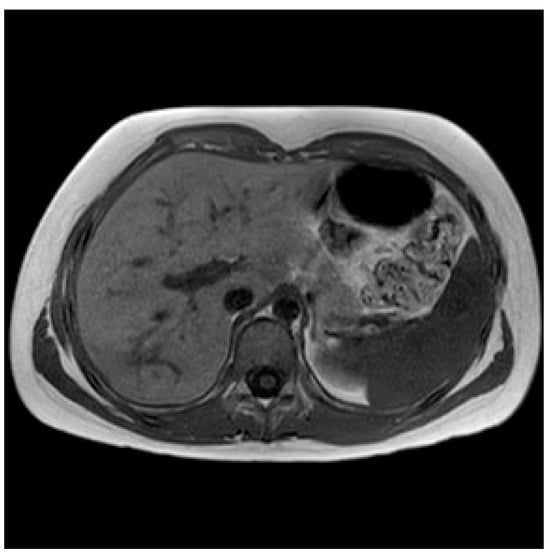

2.1. Case One—Liver Abscess

2.1.2. Initial Assessment and Hematological and Radiological Investigations